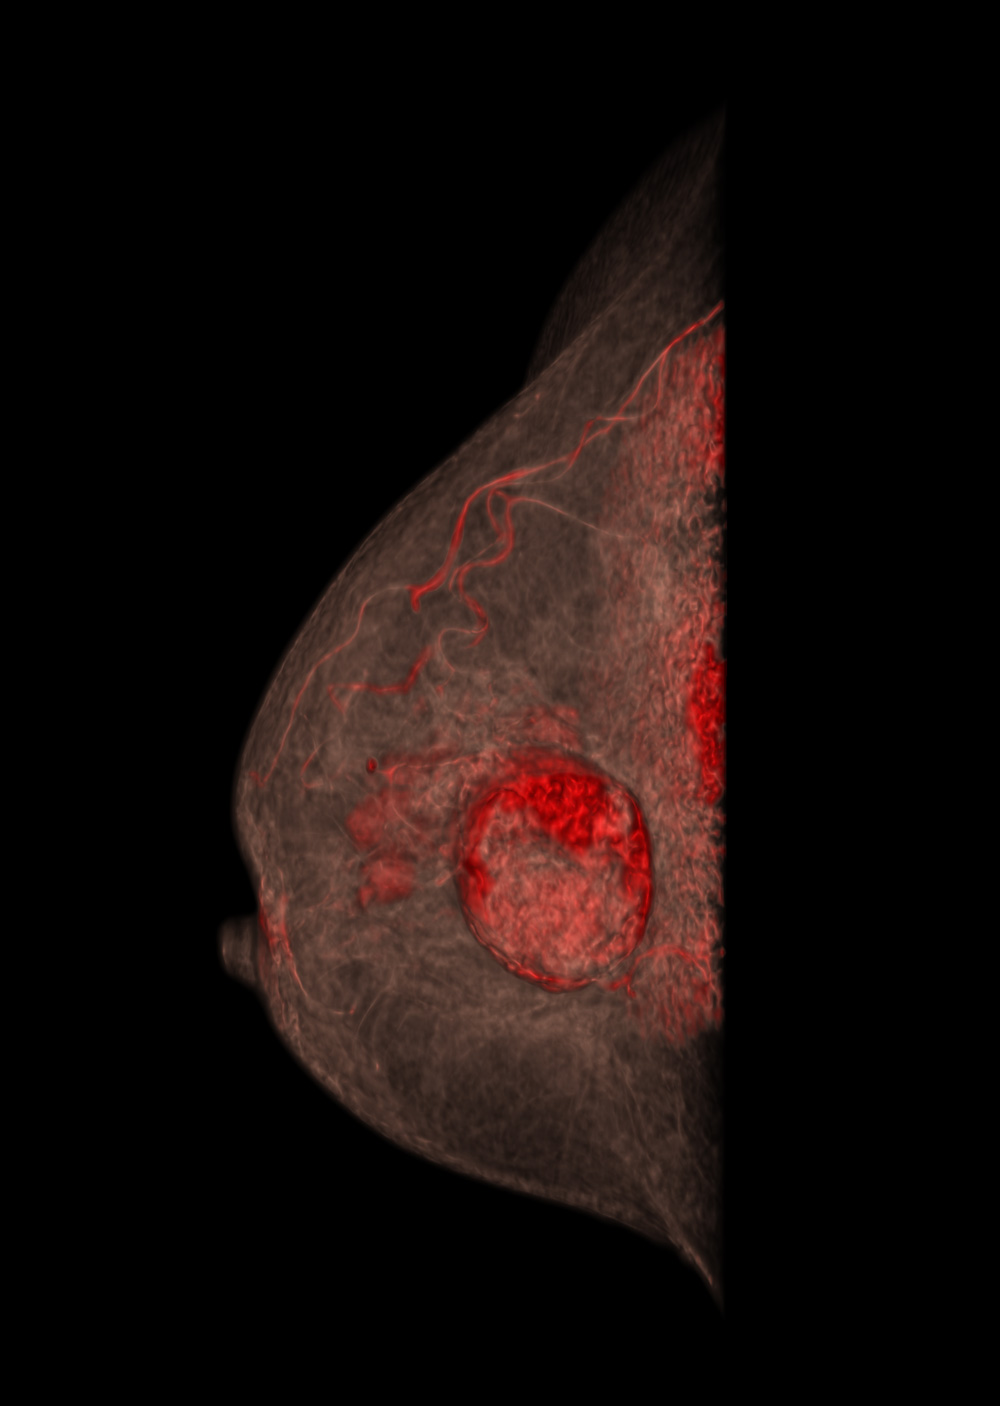

评估: BI-RADS 3

图片来源:Prof: Prof. Dr. med. Andreas Boss (USZ - 苏黎世大学医院)